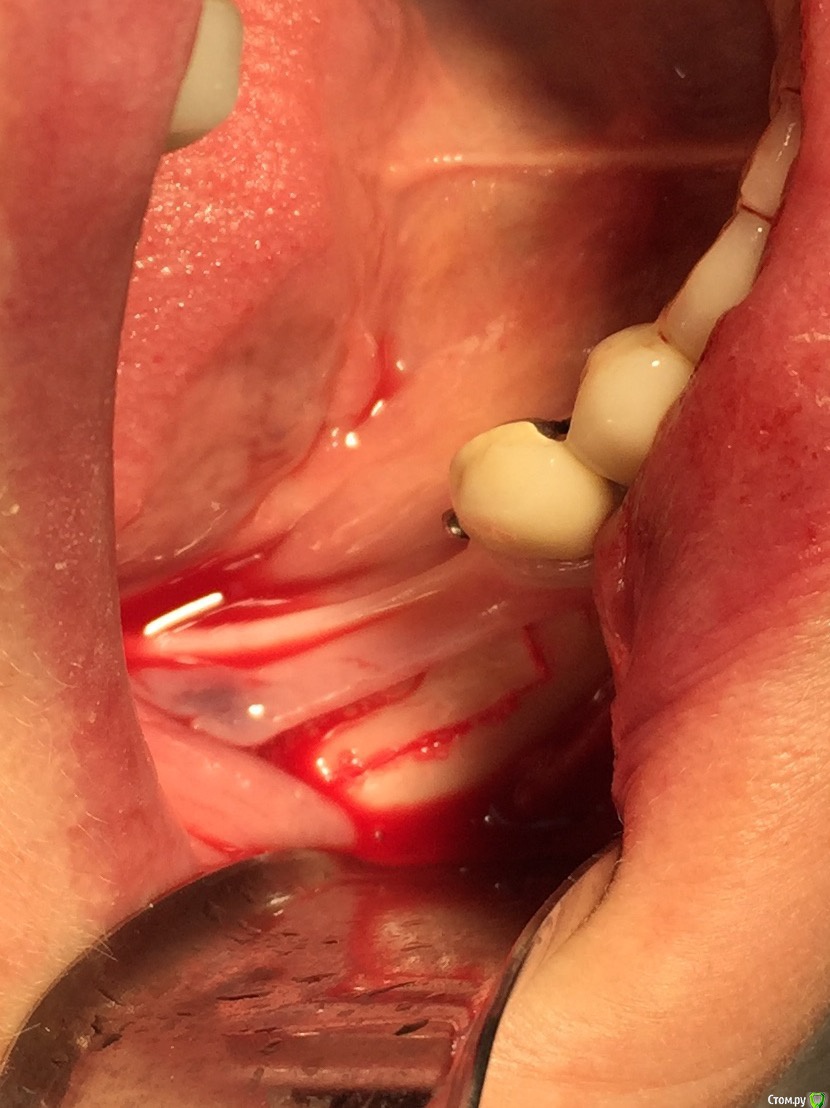

Популярный пост Глеб Митрофанов Опубликовано 22 октября, 2015 Популярный пост Поделиться Опубликовано 22 октября, 2015 (изменено) Горизонтальное расщепление Изменено 22 октября, 2015 пользователем Глеб Митрофанов 26 Ссылка на комментарий

Глеб Митрофанов Опубликовано 22 октября, 2015 Автор Поделиться Опубликовано 22 октября, 2015 круто! а срезы кт есть в этой области? и откуда треугольный ламинат брали, который в щели?Срезы есть , в телефоне найду , прикреплю . Ламинатик получился , путём истончение треснувшей крыши в дистальном отделе , думаю чего добру пропадать , заклинил его и винтом на всякий случай . Ссылка на комментарий

Глеб Митрофанов Опубликовано 22 октября, 2015 Автор Поделиться Опубликовано 22 октября, 2015 Ну вертикально же пропилы есть, да и подняли вертикально) ваш первый подобный кейс? Как ощущения?)))))) , вертикальные пропилы есть , но остеотомия горизонтальная . Кейс первый , ощущения от того , что сделал это конечно переполняют эмоциями , впереди вторая сторона . Учту опыт первой Ссылка на комментарий

Глеб Митрофанов Опубликовано 23 октября, 2015 Автор Поделиться Опубликовано 23 октября, 2015 Глеб,это вертикальное расщепление. Отлично получилось.Откуда микросом столько нашкрябали?В моём понимании вертикальное расщепление -это классическое расщепление с вертикальным продольным распилом . А стружка с дистальной крыши , который после причесывания микросом превратился в ламинат и с ветви , дистальнее распилов Ссылка на комментарий